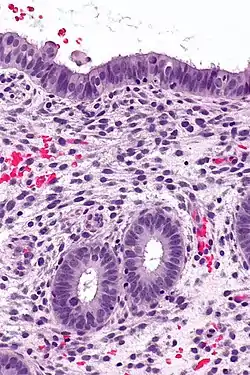

![]() Endometrium in the proliferative phase | |

The endometrium consists of a single layer of columnar epithelium plus the stroma on which it rests. The stroma is a layer of connective tissue that varies in thickness according to hormonal influences. In the uterus, simple tubular glands reach from the endometrial surface through to the base of the stroma, which also carries a rich blood supply provided by the spiral arteries. In women of reproductive age, two layers of endometrium can be distinguished. These two layers occur only in the endometrium lining the cavity of the uterus, and not in the lining of the fallopian tubes.[4][5]